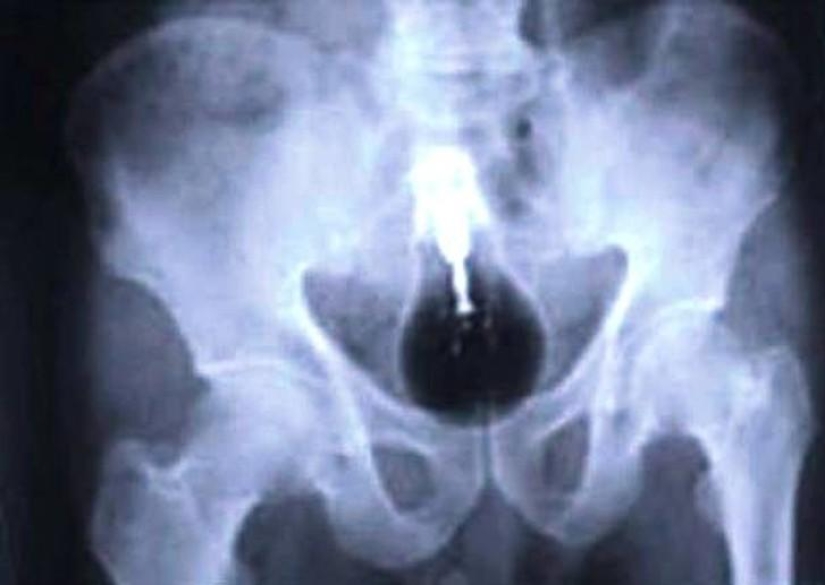

20. Mobile phone.